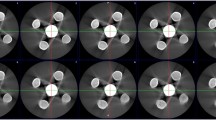

As shown in Table 1, we created a proprietary wire phantom which comprised wires of various thicknesses running parallel to the axis of rotation and held in place using epoxy resin. The wires were laid out in a cross-shaped pattern. Five wires of various thicknesses were arranged from left to right along horizontal axis as follows: 160, 120, 100, 140, 180 µm. The resolution is better in central than in peripheral region, so we put the smallest wire (100 µm) in the center and keep the same-size wires along the vertical axis. Our objective was to perform the point spread function (PSF) based on the distribution of CT pixel values vertically and horizontally along the midline of the reconstructed image. Gaussian fitting was then used to calculate the full width at half maximum (FWHM). The mean spatial resolution was obtained by averaging five FWHM values along the vertical axis (Fig. 5).

3.3 Spatial Resolution

Figure 7a and b respectively present reconstructed images of the proprietary wire phantom used in the prototype and system A. We can clearly see nine points along the two-axes in the shape of a cross. The profile in the horizontal direction presents five PSFs of wires measuring 160, 120, 100, 140, and 180 µm. The profile in the vertical direction presents PSFs of five wires of the same size (100 µm) by which to derive the mean spatial resolutions. The mean spatial resolution (FWHM) of the prototype was superior to that of system A (p < 0.05), as shown in Table 4.

Spatial resolution is a system-level performance metric affected by the size of the detector element, the size of the focal spot, and the source to detector distance as well as the methods, filters, and voxel size used in reconstruction [6]. The two systems did not differ considerably in terms of detector element size or focal spot size. The superior spatial resolution of the prototype (0.2446 mm) compared with system A (0.5179 mm) can perhaps be explained by the SOD/OID ratio: prototype (2.26) vs. system A (2.05). It might also be attributed to the fact that the source-to-detector distance of the prototype (620 mm) exceeded that of system A (520 mm), thereby permitting higher geometric magnification. The use of modulation transfer function (MTF) to quantitatively assess the spatial resolution of CBCT systems could be used to verify that the values obtained in real-world clinical environments are consistent with the values reported by the manufacturer.